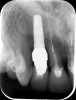

Fig 2. Radiograph showing implant was placed too deep and the diameter of the implant may be slightly larger than what was needed.

Figure 2

Fig 10. Periapical radiograph showing implant placement with abutment in place for fabrication of provisional crown.

Figure 10

Fig 12. Final periapical x-ray showing excellent bone level and implant positioning.

Figure 12